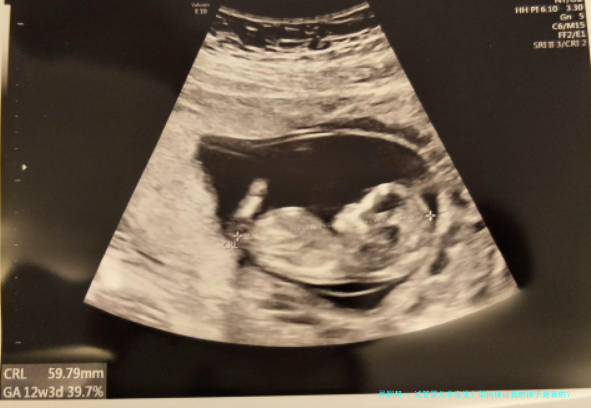

安徽“试管婴儿出生8年后被发觉放错胚胎”事件,引发注意。试管婴儿非亲生?怎么样保证我的孩子是我的?跟着人类人类辅助生殖技术的出世,给有生育困境的患者带来希望。辅助生殖技术不只是医药学技术,更是关涉到伦理问题,该怎样保障在辅助生殖技术过程顺当进行,需要从各个环节抓起,一环紧扣一环,每一步骤都至关重要。

试管婴儿技术分为第一代、第二代及第三代试管婴儿。

即是常规体外受精-胚胎移植技术(试管婴儿(IVF)-ET),是指将精子和卵子在体外培育,在卵裂期或囊胚期移植回子宫内腔着床发育。第一代试管婴儿技术主要适用于女性一方因素导致的试管助孕,优点是受孕卵中的卵子精子是当然选择,减少人造干涉。

即卵细胞质内单精子注射(ICSI),是指挑选优良单精子注射入卵子中,提高试管婴儿技术的成功率,并扩展试管婴儿技术适应症,主要适宜于男性弱精少精和女性试管助孕症。

就是胚胎移植前遗传学检测技术(PGT),鉴于“2代试管婴儿技术”的基础上,主要在囊胚期活体组织检查滋养层细胞对胚胎行染色体或特定基因检测,通过筛查健康胚胎移植以减轻不良妊娠风险。第三代试管婴儿技术平常适合于女方高龄、不明缘故反复移植失利、不明缘故反复自然流产、严重畸精子症要么染色体异样,单基因遗传性疾病、具有遗传易受感染性的严重疾病、人类白细胞抗原(HLA)匹配类型等。